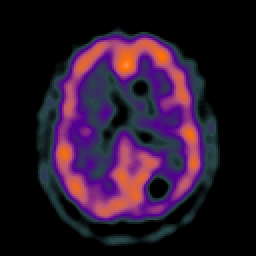

Glioma overlay -- Slice #18

[Home][Help][Clinical] Slice 18